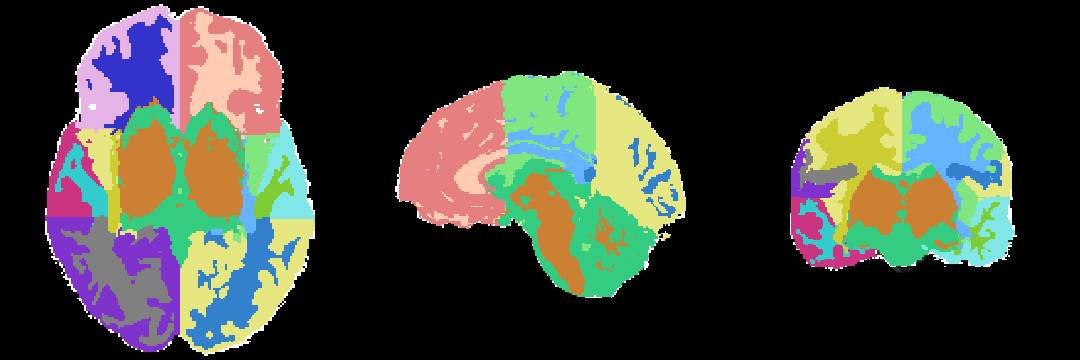

MRI Human Head pipeline for a finer-grained parcellation (TODO: Priya please provide description and proper citation)

- Step 4: Automatically segment the MRI scan into the structures of interest using EM Algorithm (Pohl et al 2007)

Anatomical Tree

The anatomical tree represents the structures to be segmented. Node labels displayed below contain a human readable structure name and in parentheses the internally used structure name.

- Root

- background (BG)

- grey matter (GM)

- subcortical grey matter (SUBGM)

- white matter (WM)

- subcortical white matter (SUBWM)

- cerebrospinal fluid (CSF)

Atlas

The atlas hes been created by Padmapriya Srinivasan and Sylvain Bouix from (PNL-BWH)

Result